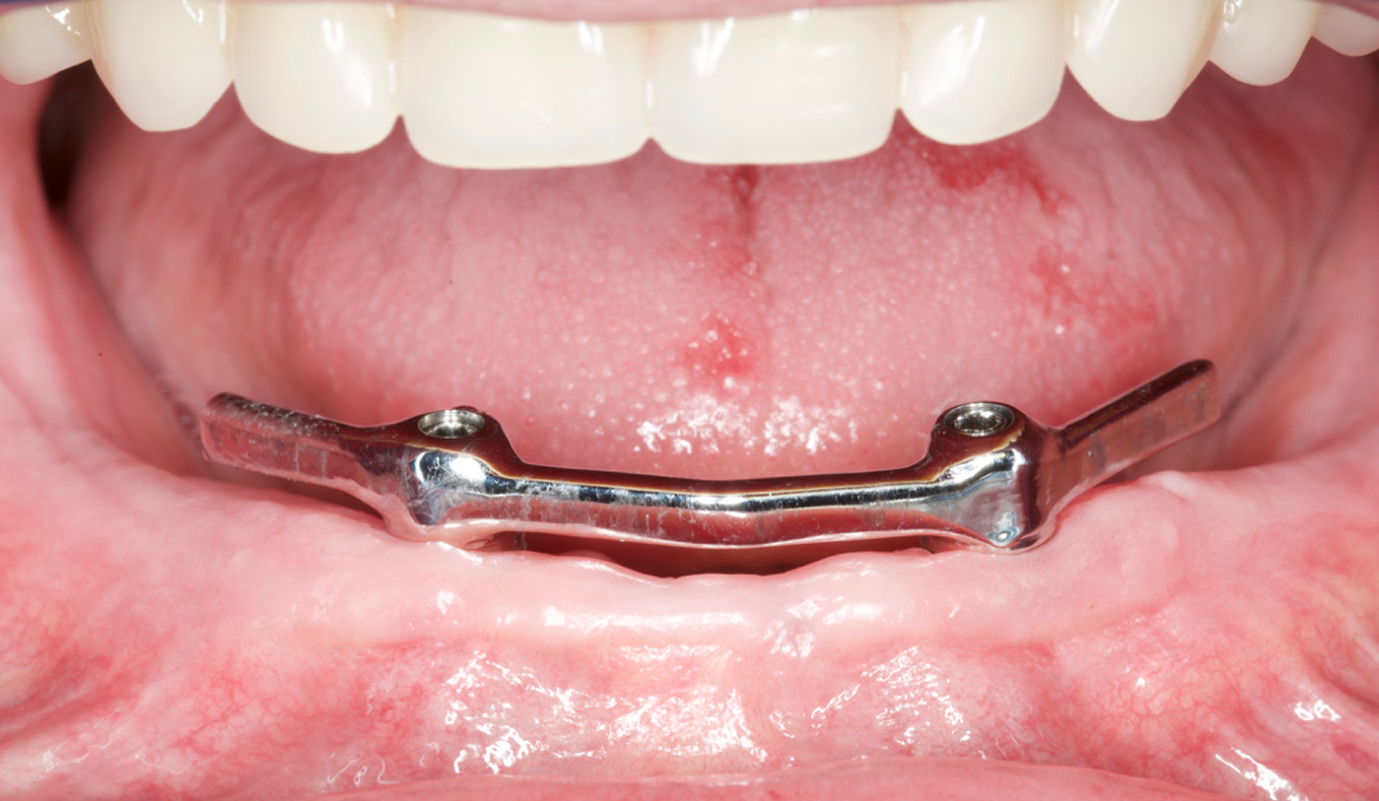

Utilizadas para a substituição de alguns ou de todos os dentes, podem ser ajustadas e apoiadas nas estruturas naturais (gengiva e dentes) ou apoiadas em implantes osteointegrados.

A colocação de implantes revolucionou o tratamento destes pacientes, permitindo a reabilitação com próteses fixas ou removíveis estabilizadas, mas mantendo os princípios clássicos de reabilitação.

Casos de próteses sobre implantes